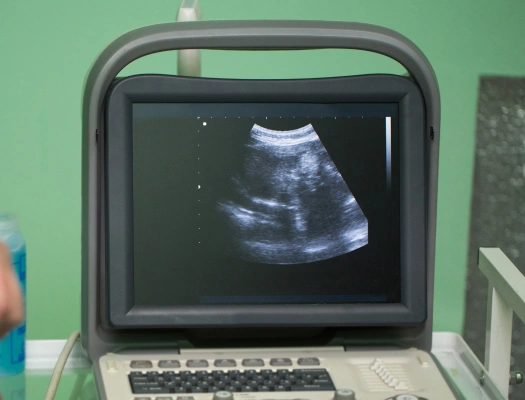

Ultrasound is a gentle, non-invasive diagnostic tool that typically does not require anesthesia. Our veterinary team ensures your pet’s comfort throughout the procedure and will explain every step so you know what to expect.

We can use ultrasound to look for conditions such as bladder stones, tumors, intestinal foreign body obstructions, pregnancy, and free fluid around the organs in the belly.